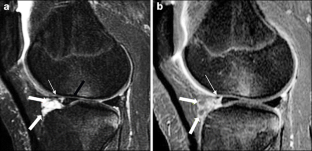

Synovium is the thin membranous lining of a joint. It produces synovial fluid, which lubricates and nourishes the cartilage and bone in the joint capsule. Synovial diseases in children can be classified as normal structures as potential sources of pathology (synovial folds: plicae, infrapatellar fat pad clefts), noninfectious synovial proliferation (juvenile idiopathic arthritis, hemophilic arthropathy, lipoma arborescens, synovial osteochondromatosis, pigmented villonodular synovitis, reactive synovitis), infectious synovial proliferation (pyogenic arthritis, tuberculous arthritis), deposition disease (gouty arthropathy), vascular malformation, malignancy (metastasis) and intra-/periarticular cysts and cyst-like structures. Other intra-articular neoplasms, such as intra-articular synovial sarcoma, can mimic synovial disease in children.